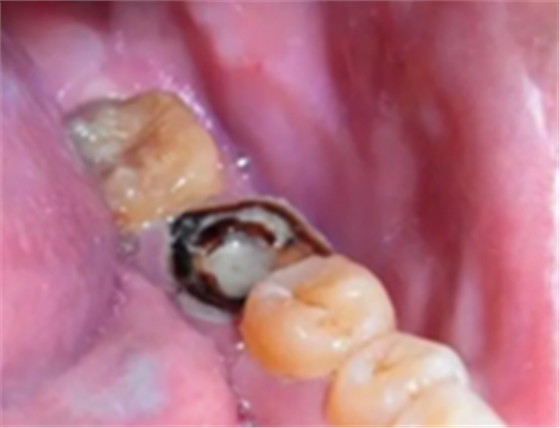

蛀牙:牙齒齲壞到牙齦以上或者牙齦以下1-2mm,牙根長度仍足夠長的話,可以保留牙根,經(jīng)過根管治療可打樁做冠修復(fù)。

嚴(yán)重蛀牙:牙冠遭到嚴(yán)重破壞的,而且牙根或牙周情況無法做樁冠修復(fù)的。